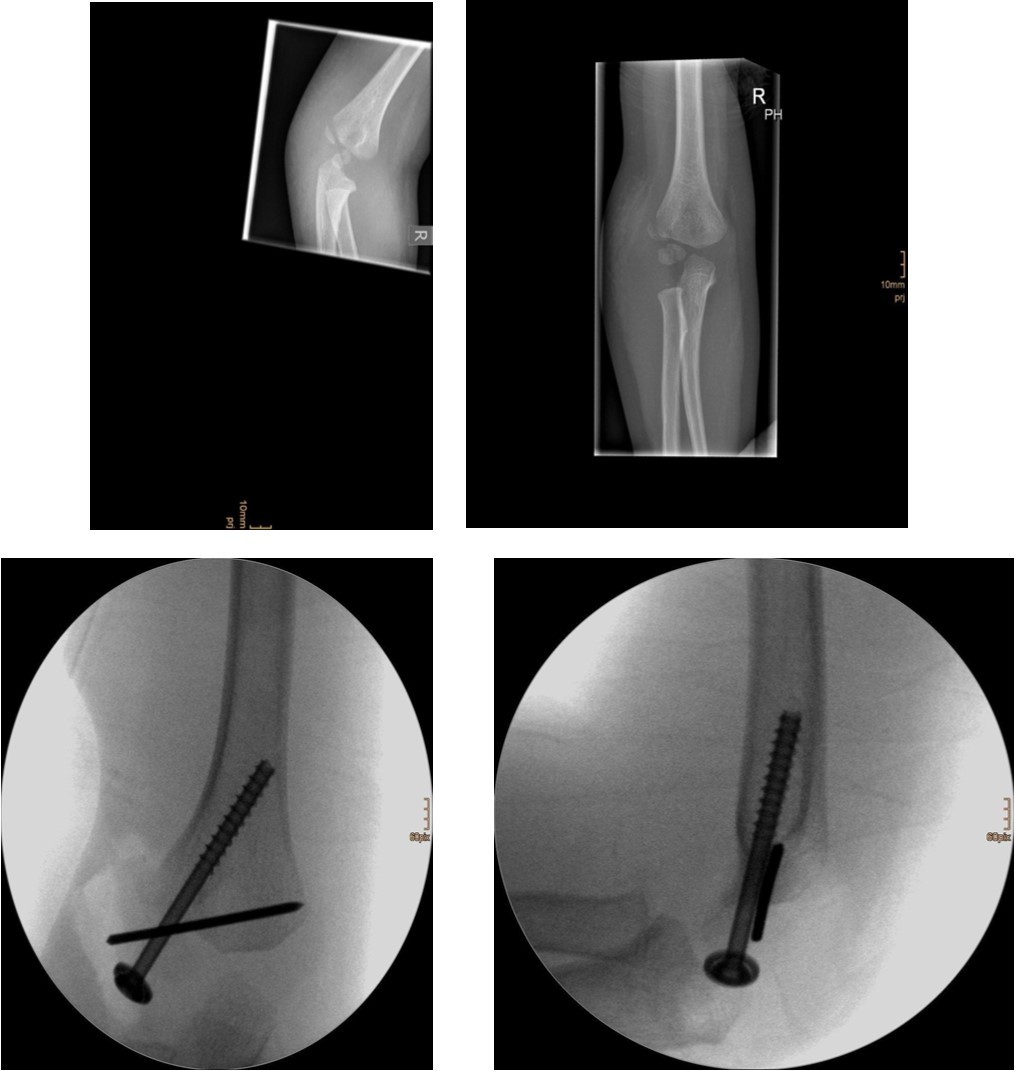

Non-displaced and stable fractures may be treated by cast immobilization with close follow-up, but fractures displaced >2 to 3 mm may indicate surgical fixation 7, 8. Surgical treatment can be done either by closed reduction and percutaneous osteosynthesis or open reduction and osteosynthesis. Figure 3.

Figure 3.9 year old male patient with a elbow dislocation and a dislocated left lateral condyle fracture which was treated by open reduction and osteosynthesis with a screw (personal collection)

Surgical fixation is either by screw, smooth K-wires or both. The K-wires can be buried under the skin or not.